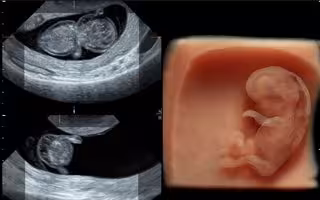

El ecógrafo 'GE Voluson E10' posee una tecnología de última generación en ecografías 3D y 4D que facilitan un diagnóstico prenatal desde la décima semana del embarazo y consigue detectar, aproximadamente, hasta el 90 por ciento de las malformaciones relacionadas con la morfología del bebé.

La tecnología de este equipo ofrece imágenes en 2D, 3D y 4D en muy alta definición con tecnología '4D HD Live' o 5D que permite la visualización de estructuras anatómicas. Aporta un gran beneficio durante el primer trimestre porque evalúa y diagnostica la anatomía de la superficie placentaria y el desarrollo de la estructura cerebral del bebé.

Este tipo de ecografías están compuestas por imágenes tridimensionales en movimiento con una renderización de alta resolución que posibilita la visualización de los órganos internos del feto.

La ecografía '4D HD Live' es capaz de detectar malformaciones desde la novena semana, permite un amplio estudio del sistema vascular gracias a sus imágenes bidimensionales, ofrece un color más nítido y natural y es un complemento de gran precisión a la ecografía rutinaria, sobre todo en embarazos de riesgo.